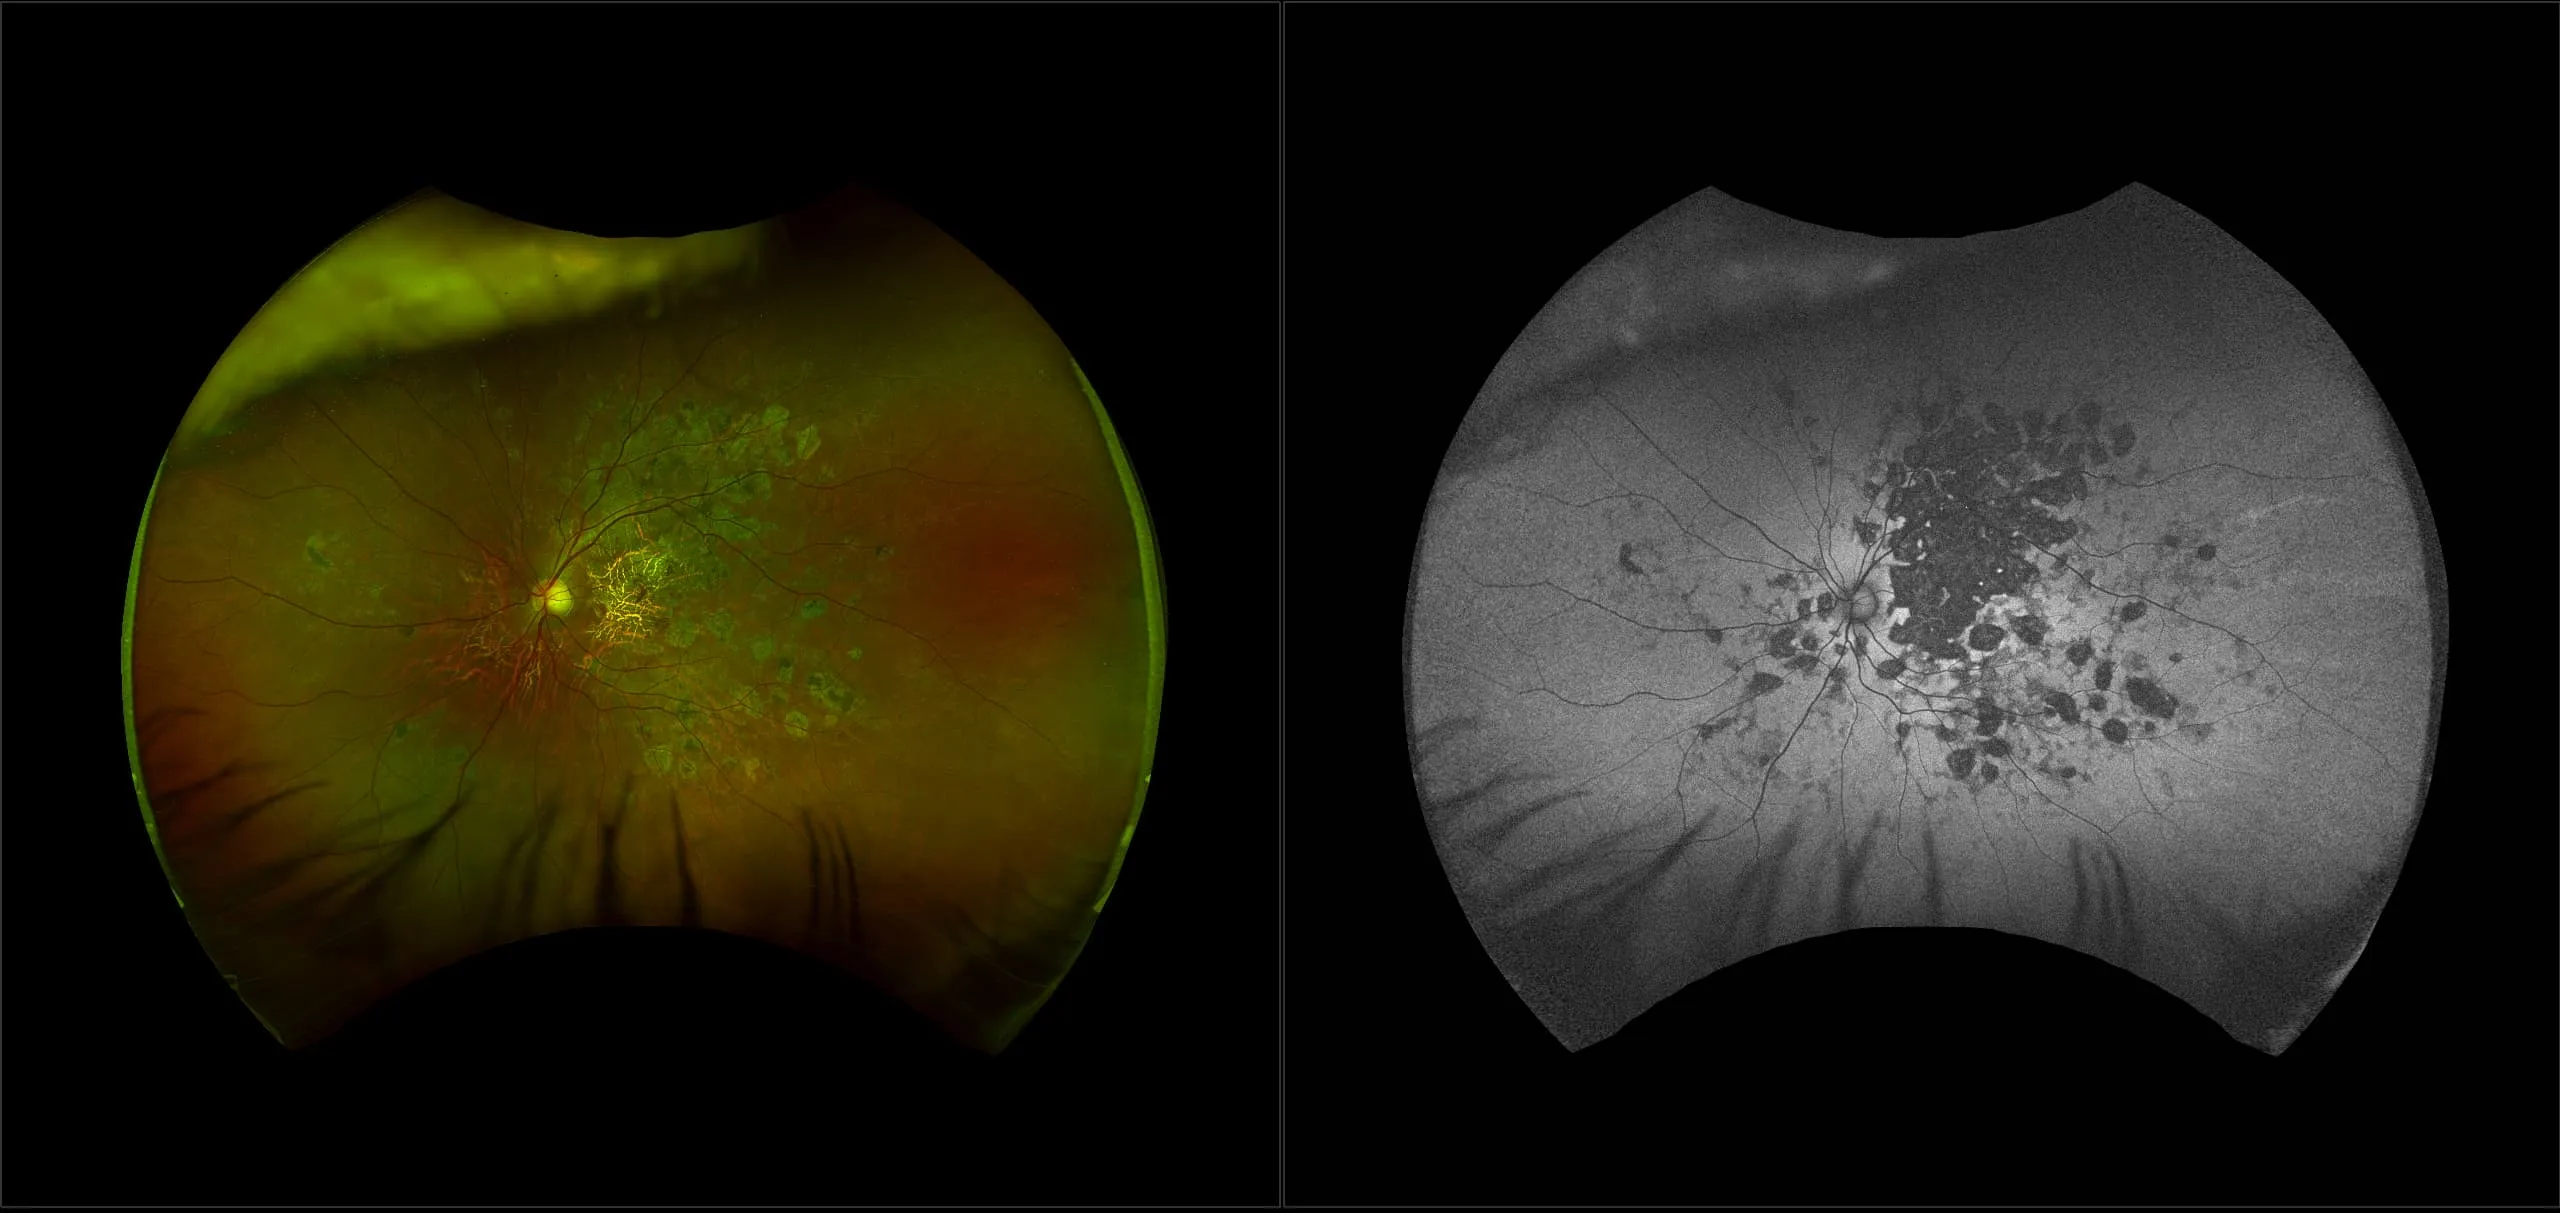

optomap® Recognizing Pathology

This material is designed as a searchable reference resource to support clinical decision-making. The information contained here should be used as general guidance when viewing optomap and OCT images from Optos devices. The differential diagnosis should be made under the direction of the responsible physician. These images were taken on the latest ultra-widefield optomap devices.

The Cases and Images

optomap Recognizing Pathology is searchable by pathology and/or optomap image modality. You may search by multiples of each selection. Each individual case is represented by the accompanying thumbnail image. Most cases include several different optomap image modalities. To view a full description of the case, please click on the thumbnail. Each image in the case will be made available through our OptosAdvance software which provides multi-dimensional visualization of digital images to aid in the analysis of anatomy and pathology. Support and pathology definitions can be found by selecting one of the buttons, above. Should you have questions, please complete the form below.